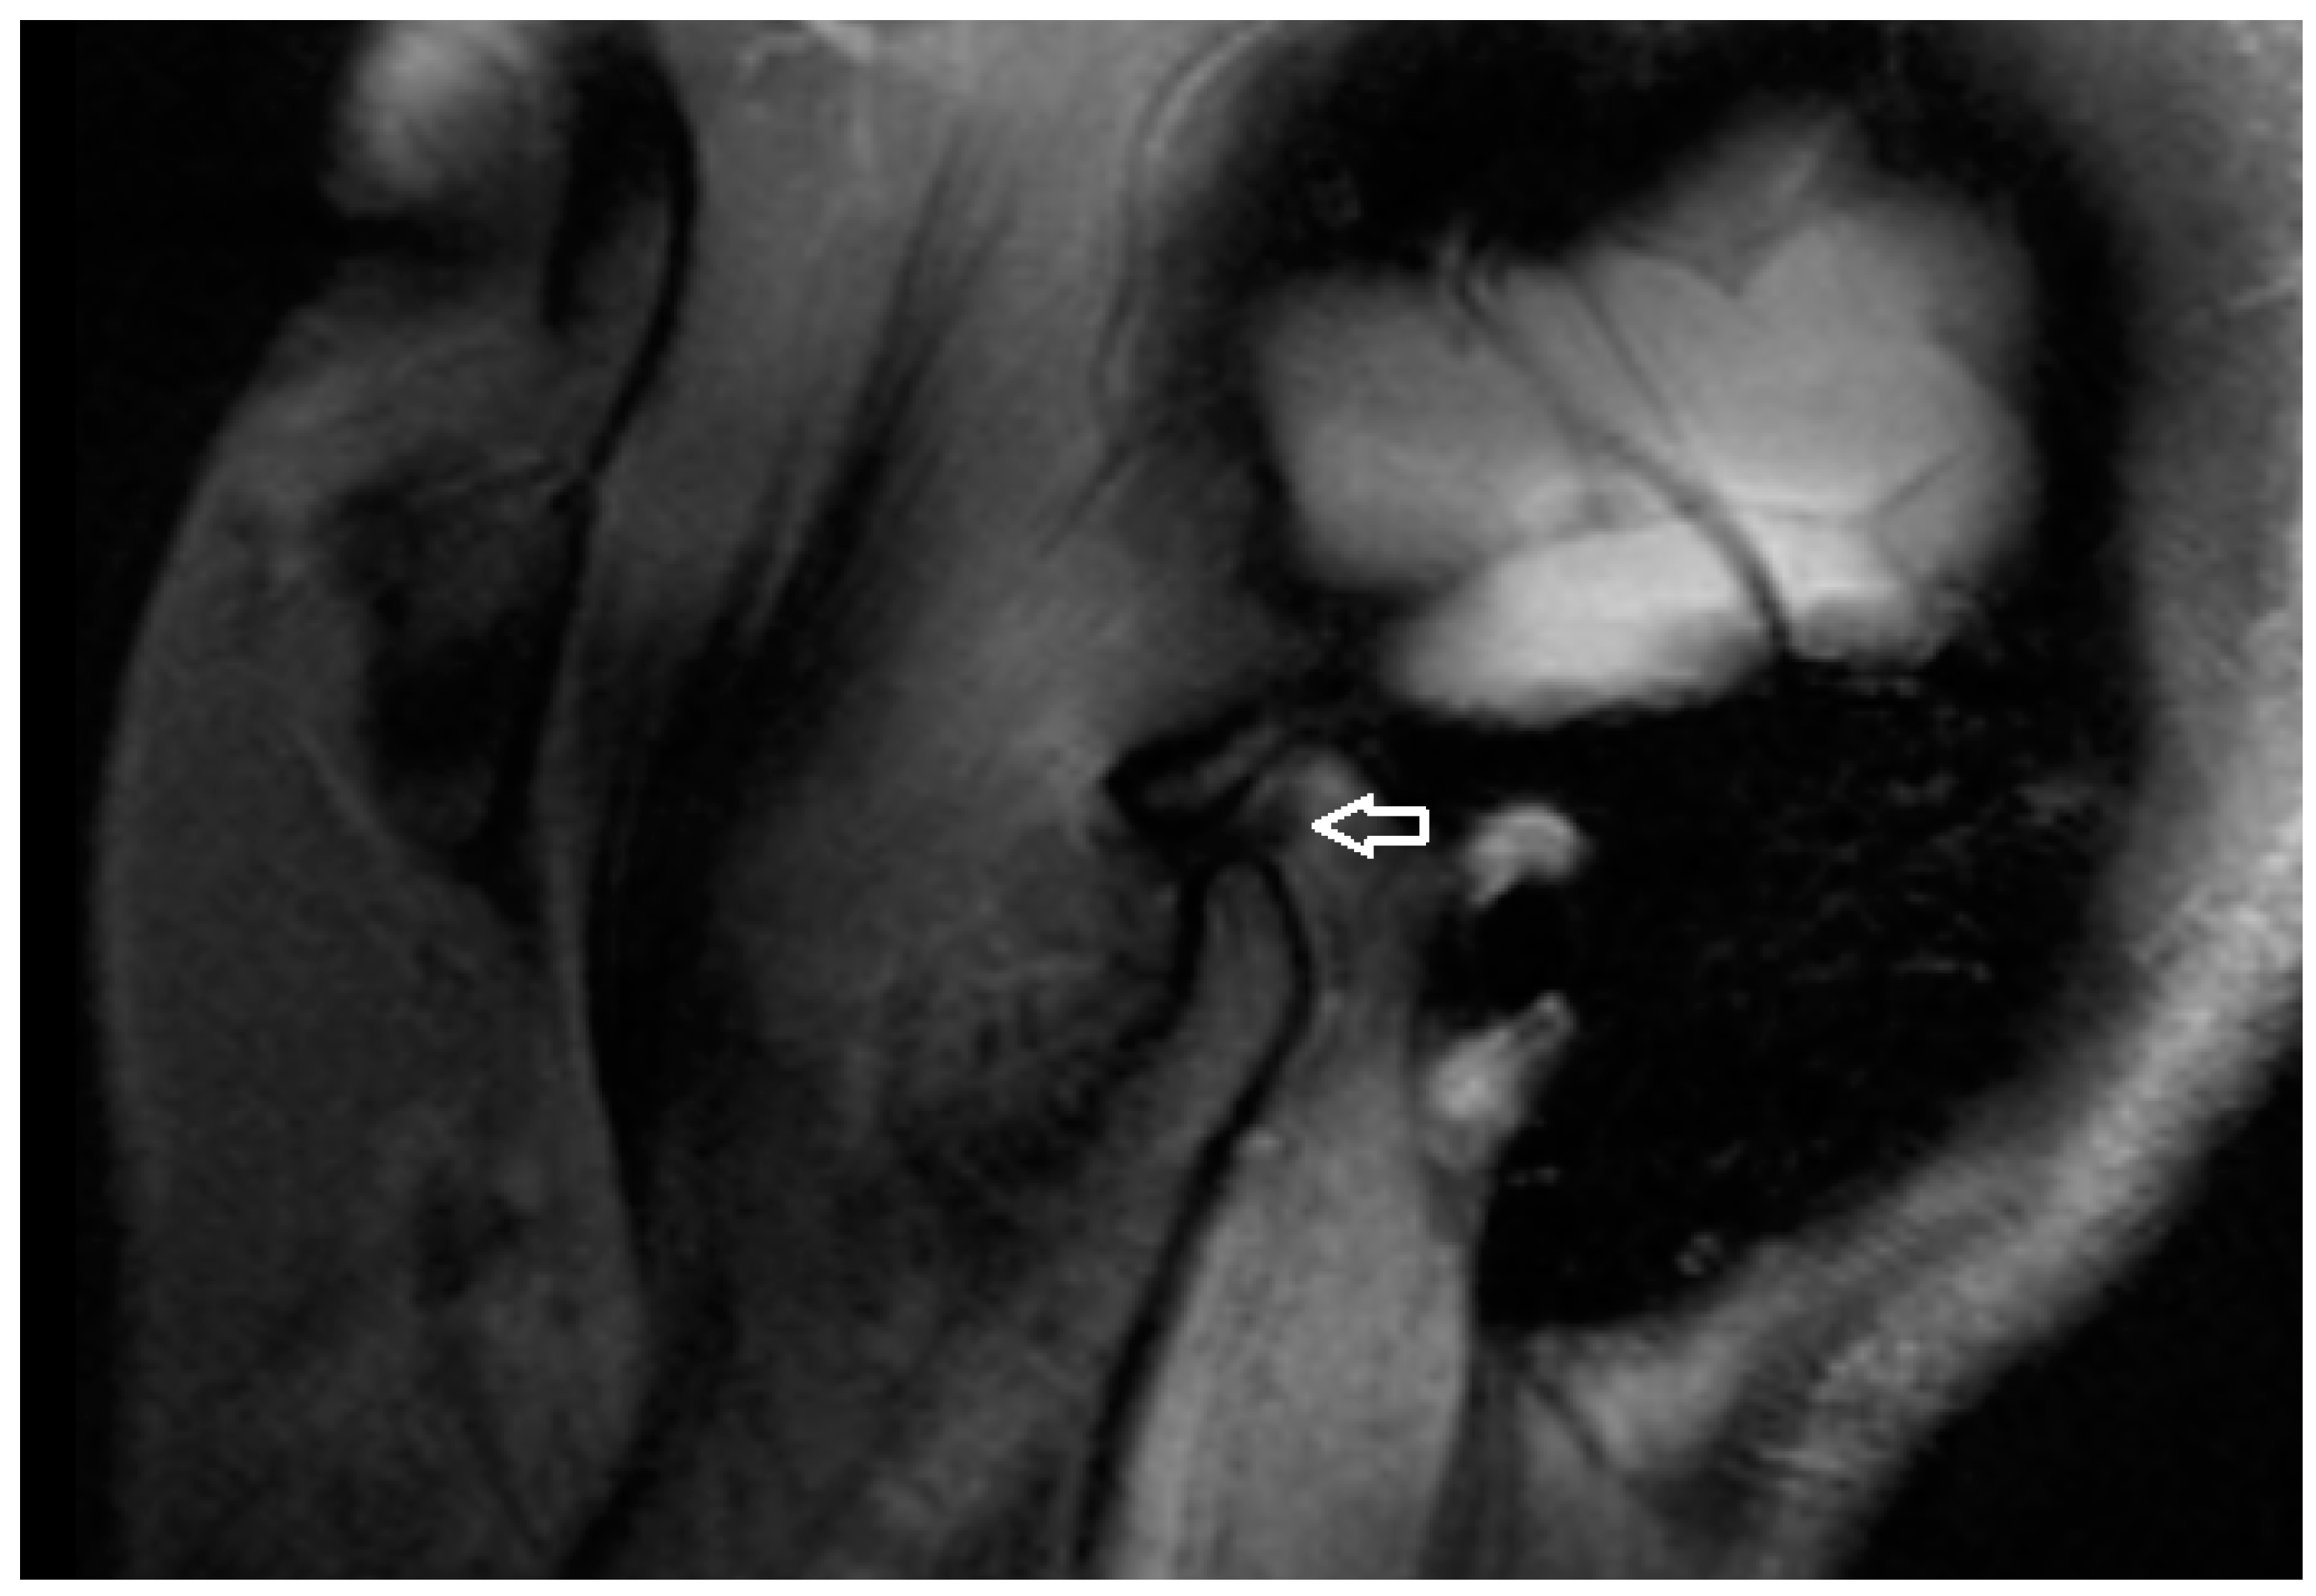

All MRI examinations were performed using a 3T MRI scanner (MAGNETOM Vida, Siemens AG, Erlangen, Germany) with a dedicated head coil. A special protocol (Table 1 consisting of three scanning phases was prepared for the study: 1. mouth closed, 2. mouth opening 2 cm (a dilator was used), 3. mouth maximally opened. In the MRI examination, a detailed analysis was performed on the TM joint structures. The presence of osteophytes and erosive changes to the bone surfaces were also assessed, as these can indicate progressive joint damage and contribute to the severity of the condition. Additionally, the condition of the articular disc was examined for any signs of displacement or degeneration, while the presence of synovial effusion was evaluated to determine the extent of joint inflammation and fluid accumulation (Figure 4).

Figure 4. PD TSE SPAIR Sagittal MRI scan (articular disc—white arrow).